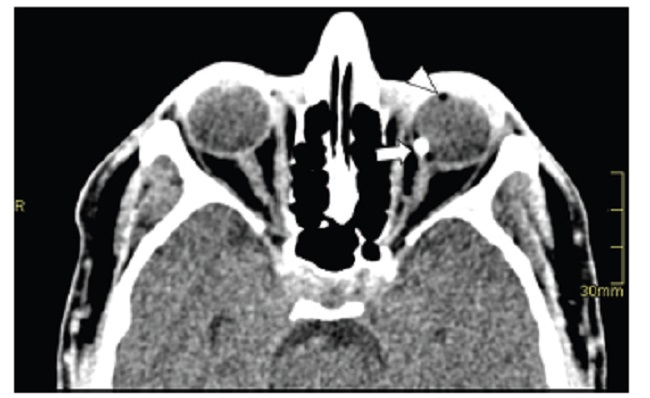

La mayoría de los cuerpos extraños en el trauma ocular son inorgánicos, como el metal y el vidrio. Los orgánicos, como la madera, son más difíciles de valorar y generan mayor respuesta inflamatoria e infecciones graves. En la TC los cuerpos extraños hiperdensos como el metal, el vidrio y el plástico se pueden identificar desde 1 mm de diámetro. Los cuerpos extraños metálicos tienen un hallazgo característico en la TC y es el destello (Fig. 11). Los cuerpos extraños de madera son más difíciles de identificar, debido a que son similares al aire en la fase aguda. Sin embargo, su forma geométrica y la medición de su atenuación ayudan al diagnóstico de cuerpos extraños de madera por TC, ya que inicialmente tienen atenuación de -100 a -200 UH (Fig. 12), la cual incrementa con el paso del tiempo debido a la acumulación de líquido. El aire presenta atenuación de alrededor de -1.000 UH. La TC tiene sensibilidad cercana al 100%, que varía según la localización y características del cuerpo extraño. La RM puede valorar el globo ocular y demostrar cambios inflamatorios asociados al cuerpo extraño cuando este no se identifica por TC. Sin embargo, está contraindicada en los cuerpos extraños intraoculares metálicos1,6.